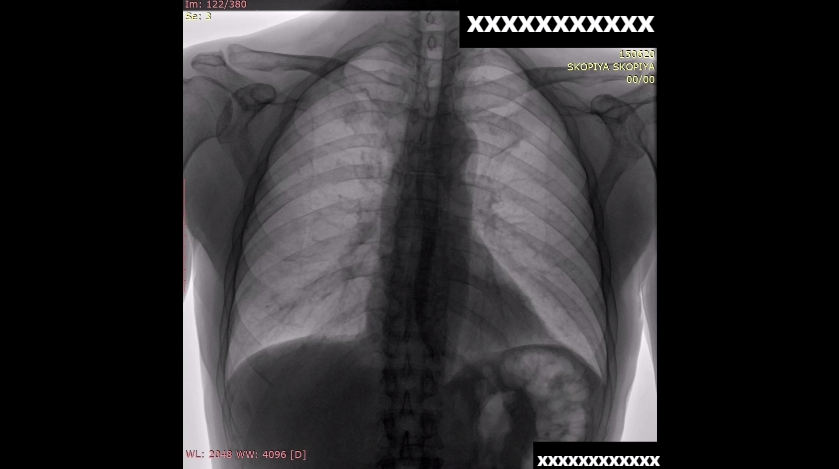

Заподозрено наличие инородного тела в пищеводе. Выполнена компьютерная томография, однако инородного тела не обнаружено. Принято решение о проведении рентгеноскопии с глотком водорастворимого контраста.

На исследовании видно, что пищевод не расширен, дефектов наполнения нет. Перистальтика живая, однако эвакуация из пищевода замедлена. Клиническая ситуация расценена как эзофагоспазм, начата консервативная терапия (ингибиторы протонной помпы, спазмолитики и нитраты) и запланировано проведение эзофагогастроскопии (ЭГДС) на следующий день. На фоне консервативной терапии пациент отметил значительное улучшение, беспрепятственно начал пить.